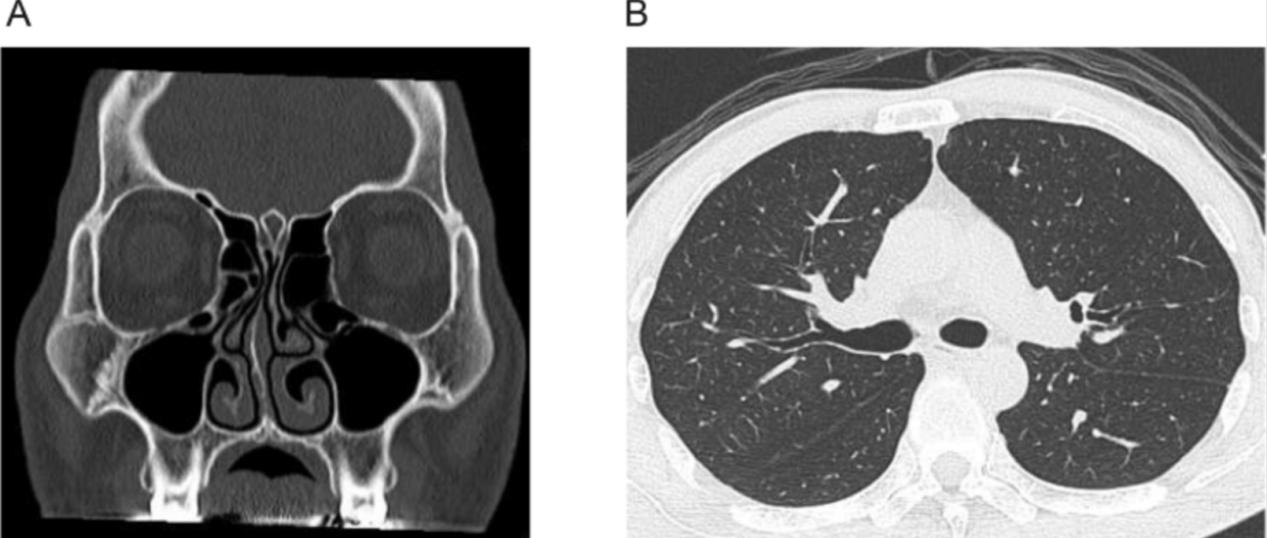

用化学发光酶免疫分析法测定抗蛋白酶3(PR3)和髓过氧化物酶(MPO)的ANCA水平,分别上升到31.2 U/ml和159 U/ml,两个参考范围均小于3.5 U/ml(表1)。同时,还检测到高效价的环瓜氨酸肽(CCP)和谷氨酸脱羧酶(GAD)抗体。然而,这个病人没有其他器官受累,例如小血管炎或类风湿关节炎。他肾功能无明显异常,无蛋白尿和尿潜血(表1和表2),计算机断层扫描显示无副鼻窦和肺部受累(图3,A和B)。然而,核磁共振图像显示两个耳蜗的T1加权图像存在对比度效应(图4,A和B),尽管T2加权图像中耳蜗的结构似乎保持不变(图4,C和D)。